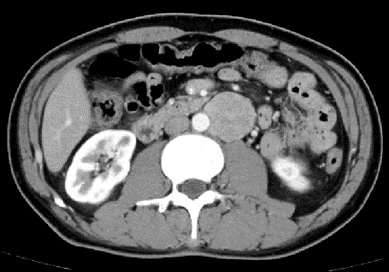

l CT:腹膜后腹主动脉旁软组织密度肿块,边界清,约4.2*4.3cm,密度不均,增强扫描皮髓质不均匀强化,实质期强化稍低,排泌期进一步减低。左肾2.0*2.3cm囊状低密度影。结论:左侧腹膜后占位,副神经节瘤?,左肾囊肿

6、 肾门下方、输尿管内侧和腹主动脉旁探及本次腹膜后肿物,目测尺寸5*5.5cm。复习CT可见肿瘤与腹主动脉关系密切,明显增强提示其血供丰富。术前阅片发现,肠系膜上动脉主干因肿瘤推挤向左侧移位。完整剥离减少出血是本次手术的重难点。且周围靠近十二指肠,操作中注意保护。